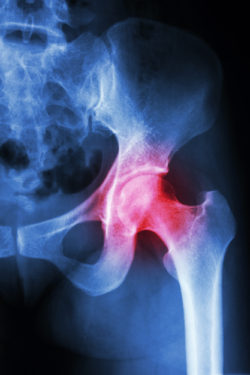

Hip surgery is a common surgery in the United States, used in order to alleviate hip pain often caused by arthritis and hip fractures. Many hip replacements are done with metal-on-metal hip implants, including the Stryker V40 hip system. Metal-on-metal devices have two metal components—the ball and the cup—that can slide or rub together as the patient moves about. Unfortunately, metal-on-metal devices carry serious risks associated with these metals.

Metallosis is a kind of metal poisoning that can occur when the metals rub together, releasing metal particles. In this case, the Stryker implant releases cobalt and chromium particles, which can move into the bloodstream. If excessive metal particles are released, they can travel through the blood and kill off surrounding tissue and nearby bone.